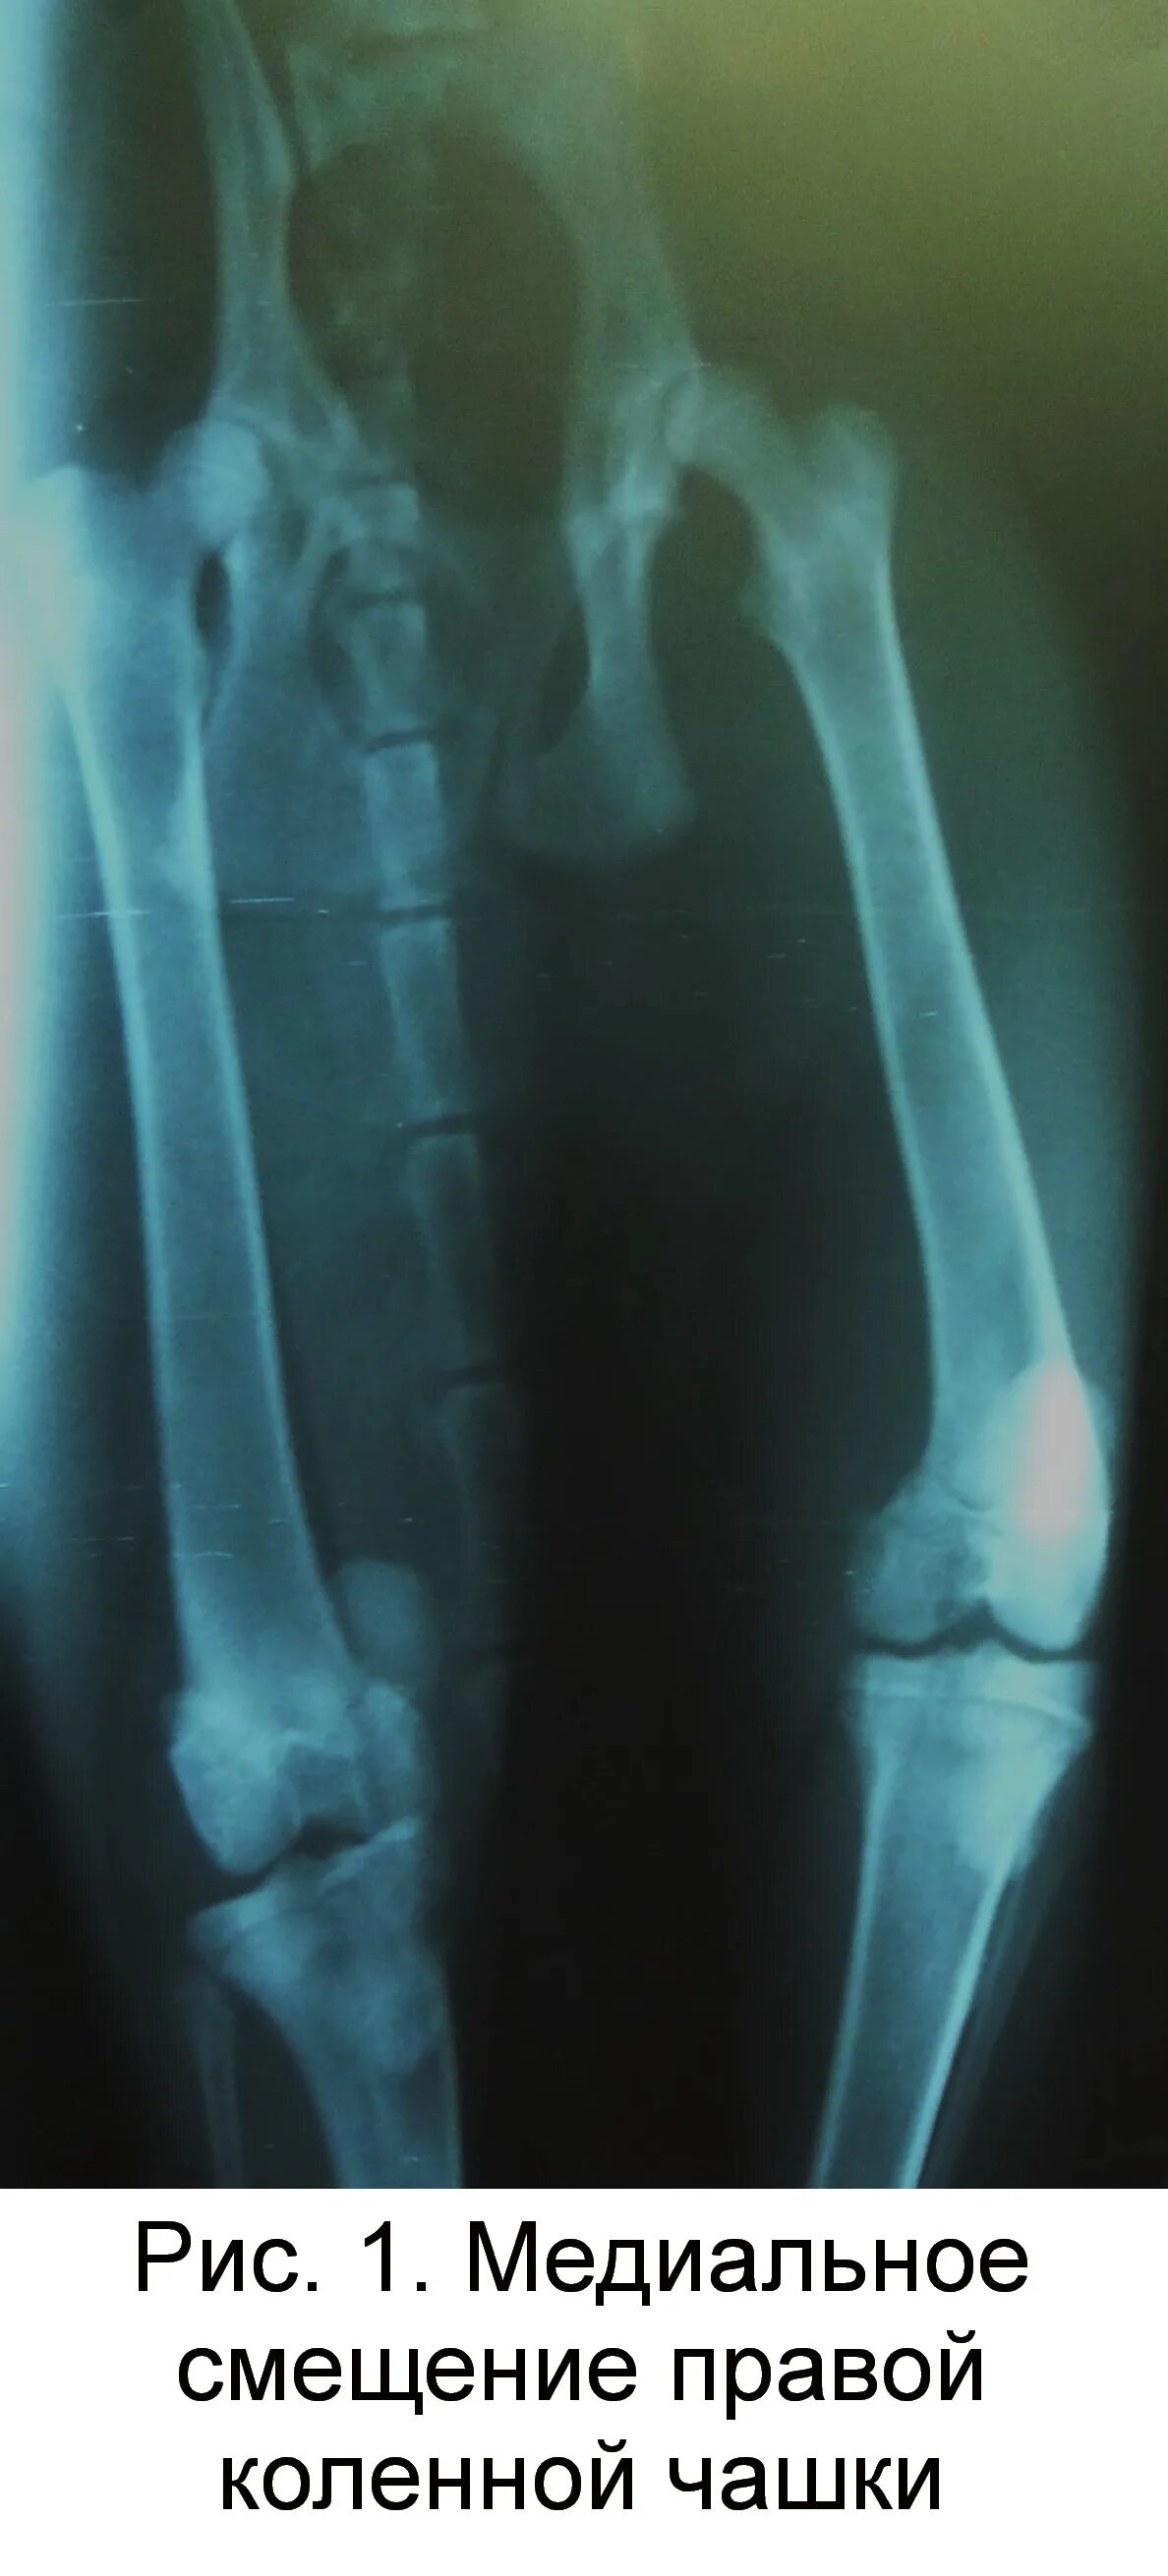

Смещение колена